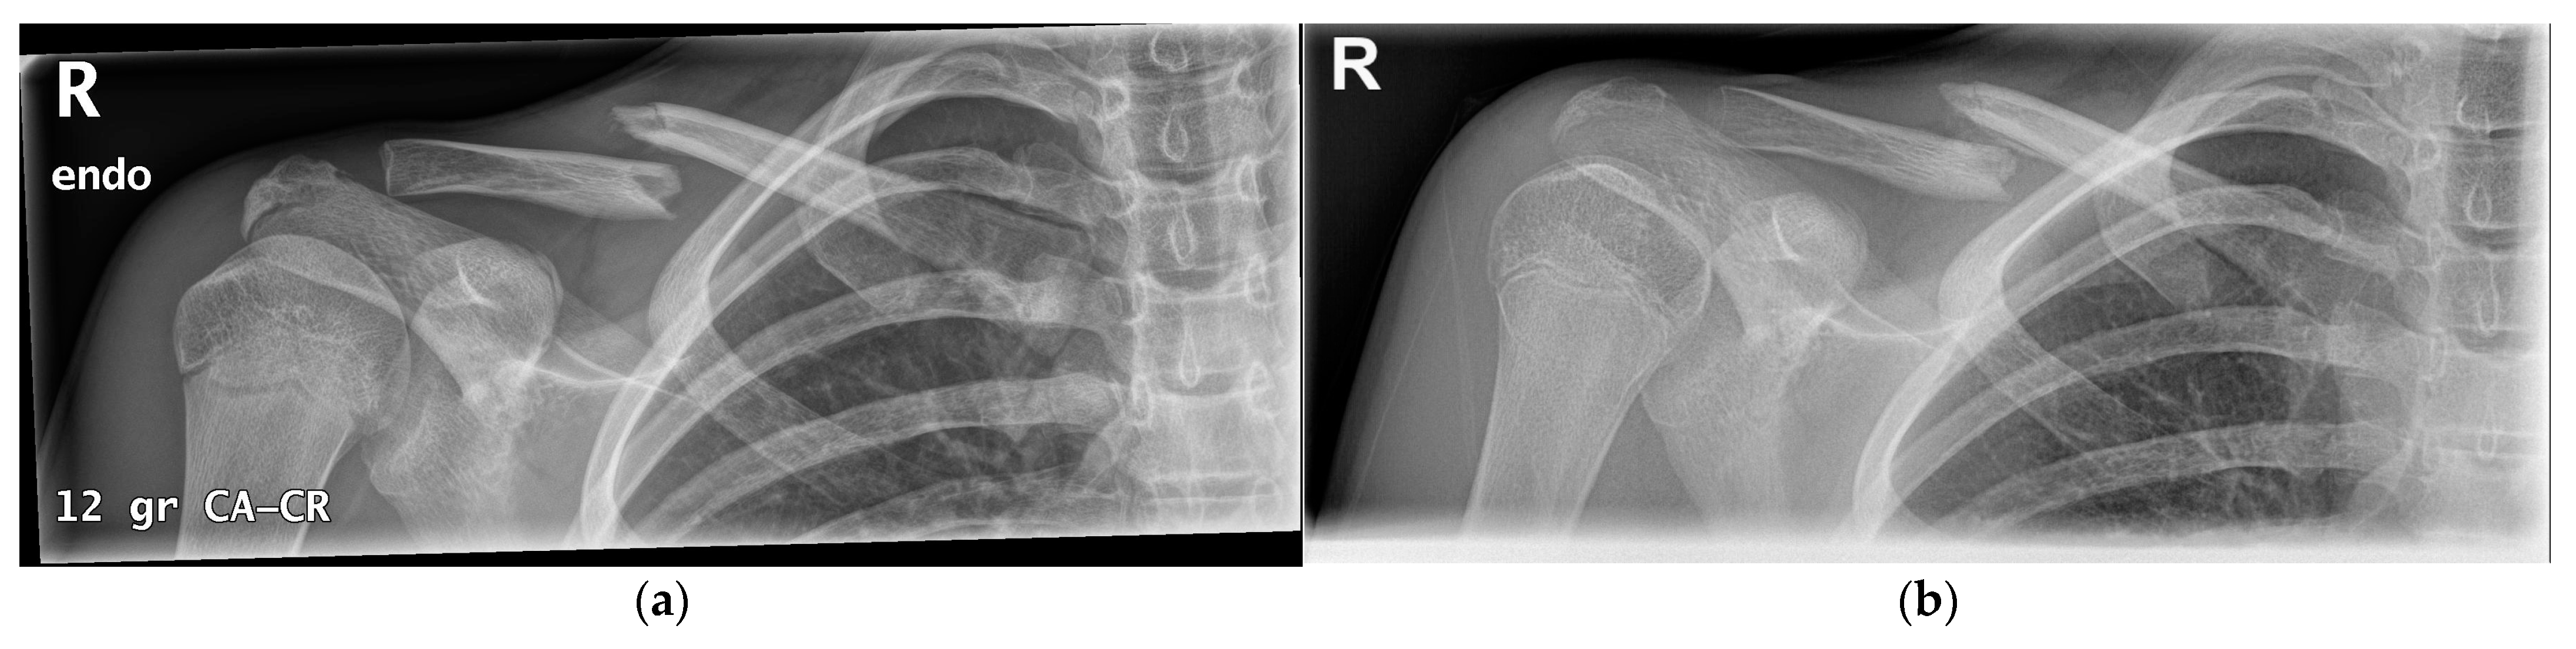

3.2. Pseudarthrosis